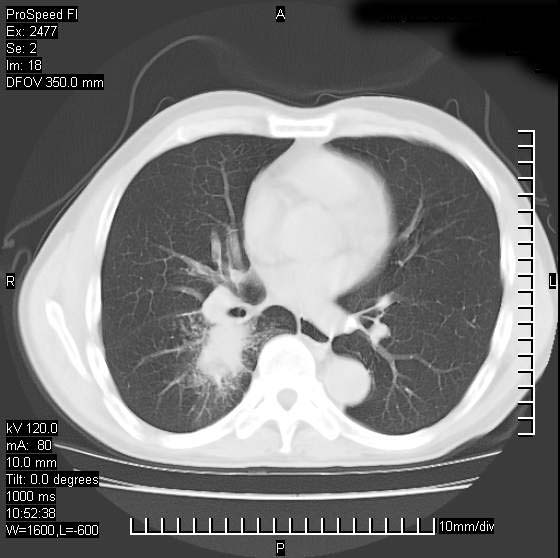

以下是引用天南地北在2007-10-9 14:29:00的发言:[br]1:右上肺结核[br]2:右肺下叶肿块:不支持肺癌,首先考虑炎性病变-肺脓疡可能性大[br]理由:1:临床病史支持,肺脓肿症状不明显应该是不规则服药造成。[br] 2:肿块边缘模糊,周围可见炎性渗出,长毛刺,内见支气管征,不过有点不规则。[br] 我感觉下肺癌这个诊断有点偏左,建议积极抗炎治疗后复查

以下是引用卜一在2007-10-9 15:55:00的发言:[br][br] [br] 1:右上肺结核[br]2:右肺下叶肿块:不支持肺癌,首先考虑炎性病变-肺脓疡可能性大[br]理由:1:临床病史支持,肺脓肿症状不明显应该是不规则服药造成。[br] 2:肿块边缘模糊,周围可见炎性渗出,长毛刺,内见空气支气管征,不过有点不规则。[br] 我感觉下肺癌这个诊断有点偏左,建议积极抗炎治疗后复查![br]支持! [br] [br] [br]

以下是引用wxy7406在2007-10-9 21:02:00的发言:[br]结合临床病史首先考虑感染性病变,但周围型肺癌不能除外,1.患者年龄偏大2.临床有咯血3.(也觉得是最重要的一点)病灶内有偏心性空洞。

以下是引用王仕学在2007-10-9 13:48:00的发言:[br]右下肺周围性肺癌可能性大,最好活检吧

以下是引用hhcckk在2007-10-9 15:18:00的发言:[br]右上肺病灶考虑结核,病灶多种形态并存(纤维化、增殖性病灶并存)[br]右下肺病灶比较难说,个人意见更趋向于“天南地北”的诊断----肺脓肿[br]1、病人有明显的寒战,高热,肿瘤病人很少出现[br]2、病灶周围的肺纹理走向柔和,没有肿瘤病灶常见的集束征[br]3、病灶边缘的毛刺较长,恶性肿瘤多为短毛刺[br]痰中血丝和病人的年龄是两个不利于良性肿块的因素,建议早点活检

以下是引用ydx_74在2007-10-9 15:53:00的发言:[br]右上肺结核,右下中心性肺癌可能大,肺门淋巴结肿大。